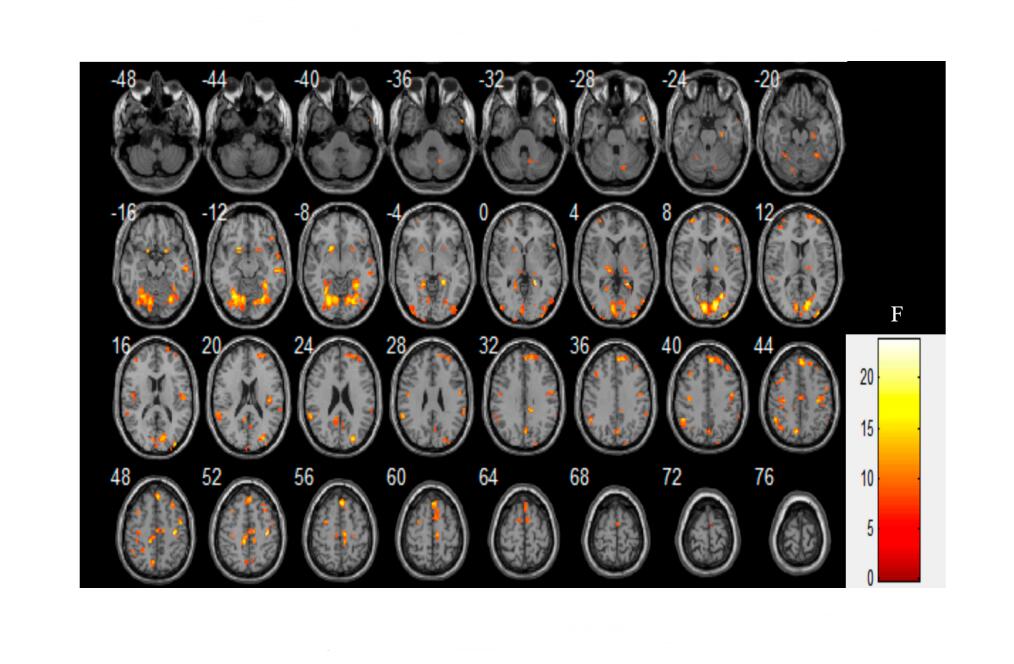

Group Differences in fALFFThree groups of subjects were analysed for fALFF values using analysis of covariance (ANCOVA) with age, gender, education level, and head movement as covariates. The results showed that seven brain clumps were statistically significant (FDR corrected, p < 0.05) and the mask signals of these seven significant brain regions were then extracted for subsequent multiple comparison analysis. See Table 2 and Figure 1 for details.

Multiple comparisons showed that the AVH group had lower fALFF values in the right lingual gyrus, right postcentral, and left supplementary motor area (SMA) than the HC group, while higher fALFF values in the right medial superior frontal, left inferior parietal lobule, left precuneus, and right supramarginal than the HC group, as detailed in Table 3 and Figure 2; the non-AVH group had lower fALFF values in the left lingual gyrus, right postcentral, and left SMA than the HC group, while higher fALFF values in the right medial superior frontal than the HC group, as detailed in Table 4 and Figure 3. However, there were no significant differences in fALFF values between patients in the AVH and non-AVH groups.

Figure 2. Comparison of fALFF in subjects in the AVH and HC groups. The AVH group had lower fALFF values in the right lingual gyrus, right postcentral, and left supplementary motor area (SMA) than the HC group, while higher fALFF values in the right medial superior frontal, left inferior parietal lobule, left precuneus, and right supramarginal than the HC group.